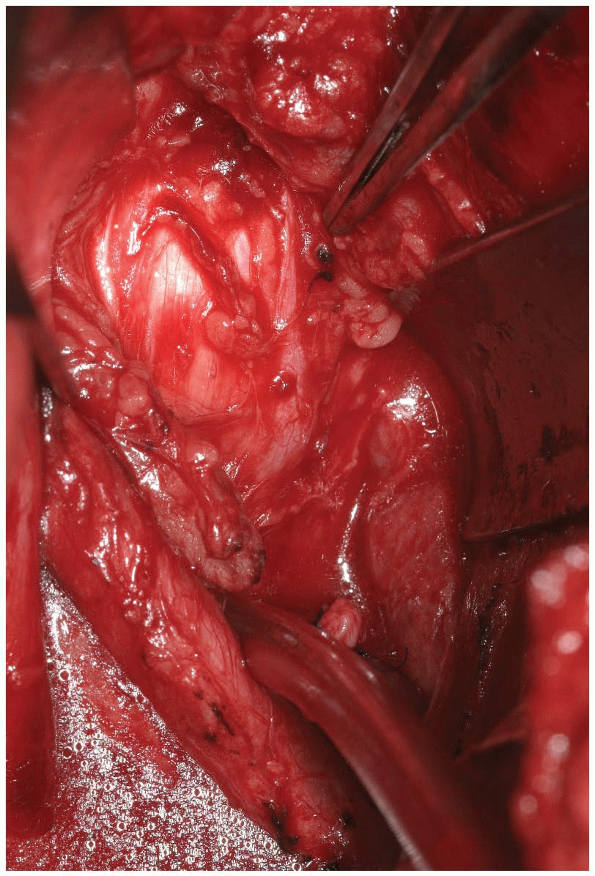

A rongeur or high-speed burr is then used

portion of the inferior lamina (Fig. 14-21). This will allow release of the insertion of the ligamentum flavum from the superior lamina of the caudal vertebra (Fig. 14-22). Immediately underneath this ligament is the epidural fat, thecal sac, and exiting nerve roots (Fig. 14-23).

After sufficient bone and ligamentum flavum have been removed the exiting nerve root should be visualized (Fig. 14-23).